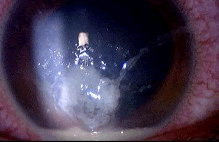

男性,25岁,左眼撞到摩托车扶手,裂隙灯检查如图,该患者的手术指征()

-

诊断晶状体半脱位(如图)的体征有()